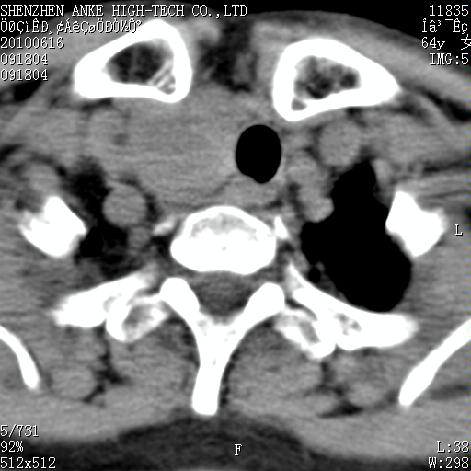

标题: CT27132:患者女,64岁,颈部及全身多处包块,现觉吞咽困难4 [打印本页]

标题: CT27132:患者女,64岁,颈部及全身多处包块,现觉吞咽困难4

右侧甲状腺占位,肿瘤可能性大,癌

右侧甲状腺癌伴右颌下腺淋巴结转移

右侧甲状腺癌伴淋巴结转移

右侧甲状腺癌伴淋巴结转移可能性大

右侧甲状腺癌伴淋巴结转移可能性大。